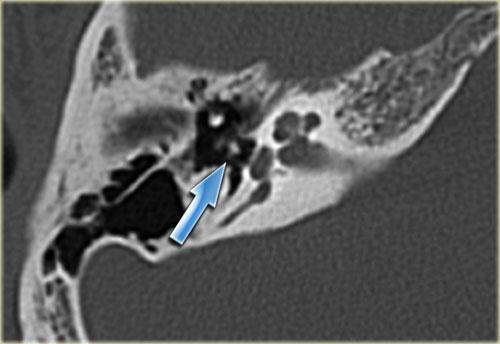

Bên trái là hình ảnh của một bé trai 16 tuổi, được khám tiền phẫu vì cholesteatoma tai phải.

Là một phát hiện tình cờ, có hình ảnh ống bán khuyên ngoài phình to (mũi tên vàng) và vắng mặt ống bán khuyên trên (mũi tên xanh dương).

Tại vị trí dự kiến của ống bán khuyên trên chỉ quan sát thấy một gờ nhỏ.

Ống bán khuyên sau bình thường.